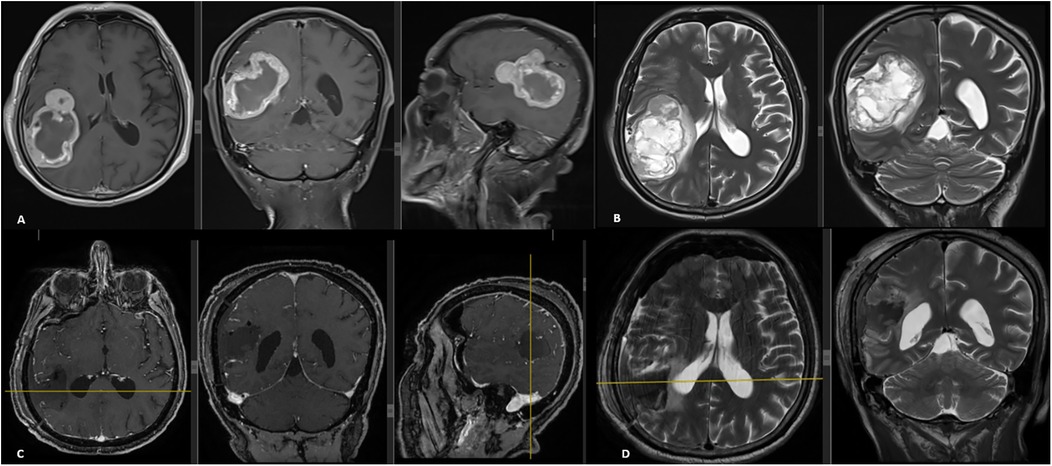

Medical scan showing a transverse section of a brain with heatmap indicating areas of activity. A red crosshair highlights a specific point. The label reads \

Figure 2. FDG-PET/CT scan demonstrating no intracranial lesions with increased uptake or causing any mass effect.

A 67-year-old male patient presented to our outpatient clinic with a complaint of low back pain that had begun 6 months prior. During the past month, the pain had started to radiate into his left leg. Neurological examination revealed muscle strength of 4/5 in the left tibialis anterior and extensor hallucis longus, along with localized tenderness upon palpation over the L2 vertebra. Magnetic resonance imaging (MRI) revealed a mass involving the right pedicle and body of the L2 vertebra. There was a 50% reduction in vertebral body height at this level, with partial tumor extension into the spinal canal and compression of the thecal sac from the right side (Figures 1A,B). The lesion appeared hypointense on T1-weighted images and hyperintense on T2-weighted images and exhibited diffuse contrast enhancement. An FDG-PET/CT was also performed, which demonstrated increased uptake at the L2 vertebra (SUVmax, 12.5), suggestive of metastasis. No intracranial lesions exhibited increased uptake or produced mass effect on the FDG-PET/CT (Figure 2). Based on these findings, the lesion was initially considered a potential metastatic tumor, and surgical intervention was scheduled. Surgery was performed via a posterior approach. A total laminectomy at L1 and right-sided hemipartial laminectomy at L2 were conducted to achieve subtotal decompression and tumor removal. Posterior stabilization from T11 to L4 was achieved using bilateral pedicle screws, with unilateral placement at the L2 level on the left side (Figure 1C). The lesion was entirely extradural. Histopathological examination revealed nodular tumor tissue within a rich vascular background, characterized by focal, prominent epithelial proliferation. The tumor cells were predominantly clear, partially physaliphorous, and partially eosinophilic with abundant cytoplasm, showing low-grade atypia. While mucin was present in small areas and there were single-layered cell patterns resembling adenoid structures, well-formed glandular architecture was not identified. Immunohistochemically, the tumor was strongly positive for vimentin, CDX2, TTF-1 (in 25% of cells), epithelial membrane antigen (EMA), and Pan-CK (5/6/8/18). It was negative for S-100, CK-20, CK-7, CK-5/6, CD10, and renal cell carcinoma (RCC). Brachyury staining was not performed. Due to the absence of S-100 positivity, a diagnosis of chordoma was ruled out. Although CDX2 positivity indicated intestinal differentiation, the lack of CK7 and CK20 expression, which are typically seen in gastrointestinal tumors, argued against that origin. Possible primary sources considered included adrenal, hepatic, and prostatic carcinomas. A definitive diagnosis could not be established, and the lesion was interpreted as a metastasis of clear cell carcinoma from an unknown primary. The postoperative course was uneventful, his symptoms were resolved, and the postoperative neurological examination of the patient was unremarkable. Stereotactic radiosurgery (TruBeam) was administered, delivering a total dose of 30 cGy in 10 fractions to the tumor site.

Chordomas can metastasize, but this typically occurs in the advanced stages of the disease (30). The lungs are the most common site of metastasis, with younger patients being more frequently affected (8). Other potential metastatic sites include the liver, lymph nodes, bones, and cerebrospinal fluid dissemination (8, 31). Steenberghs et al. (32) and Badwal et al. (33) have reported spinal and meningeal metastases originating from intradural chordomas. Although intradural chordomas are considered to have a better prognosis (3, 6), they may still tend to metastasize (30). Cases of seeding metastases from cranial chordomas have been reported previously (8, 30). Surgery for intracranial chordomas has been suggested as a possible factor contributing to surgical seeding metastasis (30). However, this remains speculative, as no published cases include spinal MRI at the time of diagnosis and/or surgery for intracranial intradural chordomas (7). Kawanabe et al. reported the only case demonstrating spontaneous coexistence of spinal and cranial intradural chordomas in the same patient (7). Our case represents an exceptionally rare example compared to those reported in the literature. In this case, a classical spinal chordoma was diagnosed and surgically treated. At the time of diagnosis, a PET/CT scan showed no intracranial lesions. Six years after the initial surgery, the patient developed an intracranial mass. It is difficult to definitively classify this lesion as a metastasis from the spinal chordoma, but prior imaging clearly demonstrated that the intracranial lesion was not present at the time of the initial spinal chordoma diagnosis. Another important point is that the dura was not opened during either of the two spinal surgeries, meaning the spinal chordoma was located extradurally. It is also possible to speculate that a small EP-type lesion may have migrated to the brain parenchyma during embryonic development and remained dormant for years before differentiating into an intradural chordoma. It is possible that this lesion may have remained undetected in PET/CT scans. Although the mechanism is difficult to explain, to consider the current lesion as a metastasis occurring in the opposite direction than typically expected—that is, spreading from the spinal column to the cranial vault, is also possible.